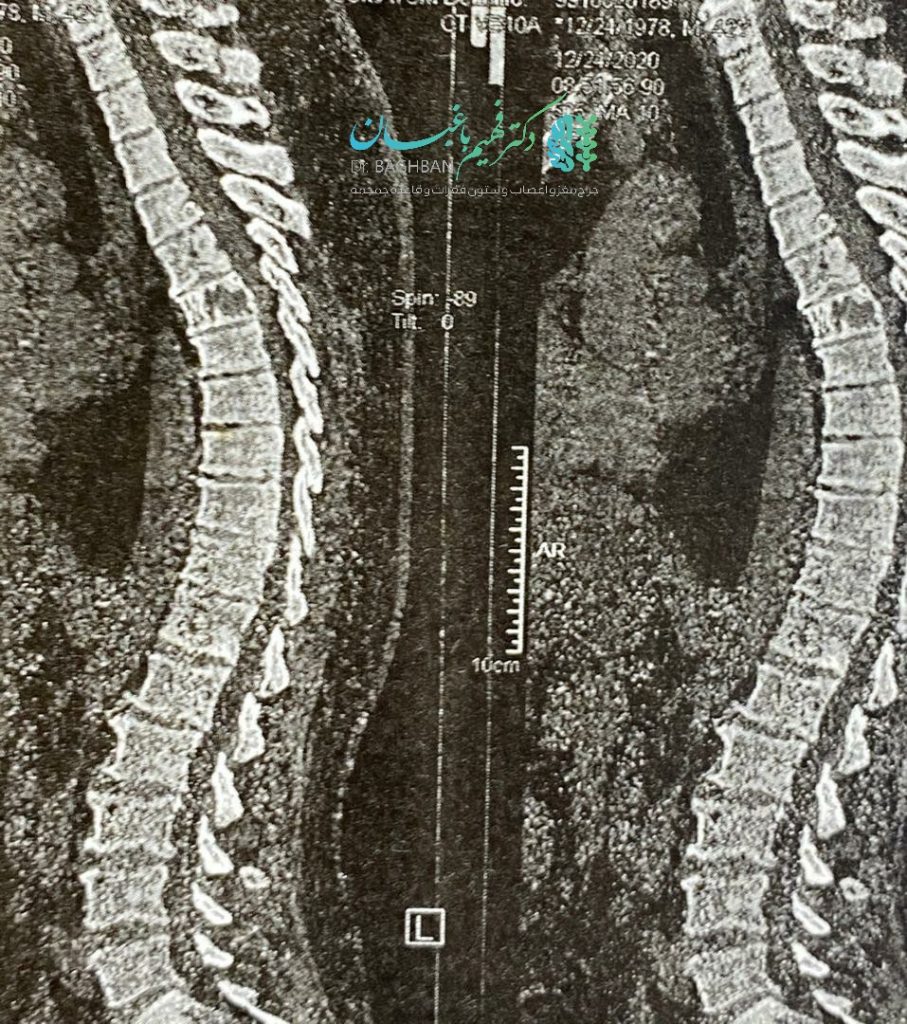

آقای میانسال با ضعف پیشرونده اندام های تحتانی و بی اختیاری ادرار و مدفوع مراجعه کرده بودند. تومور همانژیومای مهاجم مهره ششم توراسیک که سبب آسیب نخاع شده بود. بیمار با نورومانیترینگ دائمی تحت عمل جراحی قرار گرفتند که ابتدا نخاع آزاد و سپس کل مهره توسط سیمان ،ورتبروپلاستی شد. با تشکر از آقای دکتر حسین زاده، همکار محترم جراح اعصاب که عمل با یاری ایشان صورت گرفت.

تصاویر قبل و بعد ازعمل